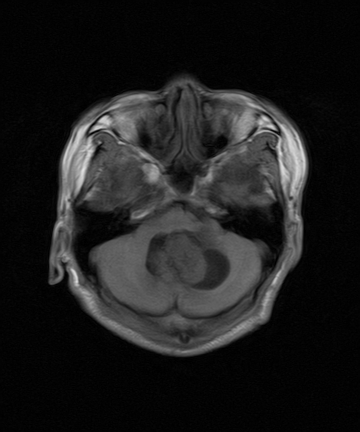

四脑室区见混杂信号占位影,脑室系统扩张明显,临近结构显著受压称位,患者52岁,多考虑室管膜瘤可能性大

应该是来源于小脑蚓部的占位,如血管母细瘤或星形细胞瘤

考虑第四脑室室管膜瘤【血供丰富血管母细胞瘤可能】并梗阻性脑积水;部分性空蝶鞍;左侧上颌窦粘膜下囊肿。

1、四脑室肿瘤并并脑积水。考虑室管膜瘤可能性大,脑膜瘤等排。

小脑蚓部胶质脑膜瘤突入四脑室;肿瘤内见血管流空信号和钙化信号.

比较典型的脉络丛乳头状瘤并脑积水,鉴别小脑蚓部血管母细胞瘤。